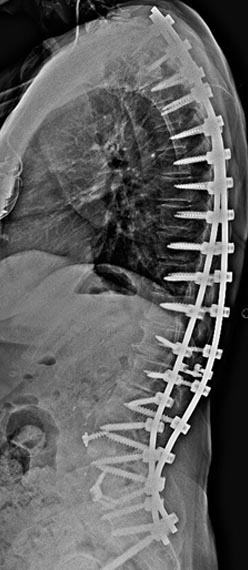

21 year old woman with very ridged 90 degree Scheuremann's kyphosis corrected to 40 degrees.